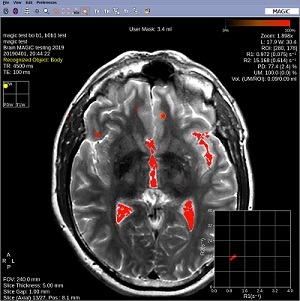

Figure 1. Example of a user mask

• A ROI is created around the segmented region.

• If the segmented region overlaps with existing user mask the ROI is created around the whole region.

• In the addition mode the region is added to the user mask

• In the subtractive mode, the region is subtracted from the user mask.

• Note: that when used on contrast weighed images, the functionality is primarily designed for easier selecting findings small areas of interest.